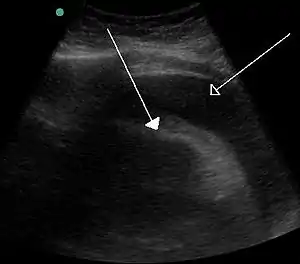

There can, however, be disastrous consequences when tamponade occurs as a result of health problems, as in the case of cardiac tamponade. In this situation, fluid collects inside the pericardial sac. The pressure within the pericardium prevents the heart from expanding fully and filling the ventricles, with the result that a significantly reduced amount of blood circulates within the body. If left unchecked, this condition will result in death.